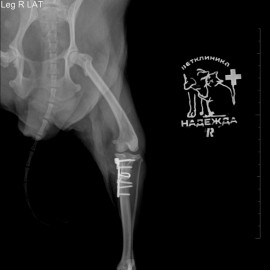

К нам в клинику обратились с жалобой на хромоту на правую заднюю конечность. Беспокоило в течение нескольких дней. После проведенных исследований поставлен диагноз: остеоартрит правого коленного сустава, пателлярный вывих коленного сустава, разрыв передней крестообразной связки. Была проведена операция TPLO, латеральная транспозиция шероховатости правой большеберцовой кости.

Снимки 2-3 после операции.